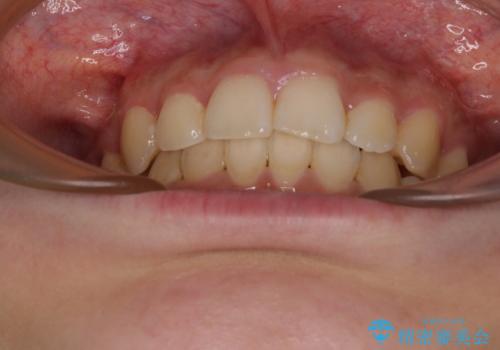

下顎前歯が隠れて突出した口元 ワイヤー装置での抜歯矯正

骨格的な左右差がありましたが、何とか当初予定していた期間で、左右対称の咬み合わせに仕上げることができました。